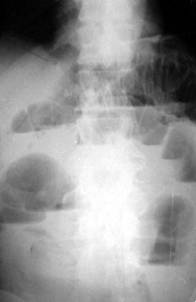

Науқас Ш,13 жаста. Нәжістің жоқтығына, ішінің ұстамалы ауруына шағымданады. Тері жамылғысы бозарңқы, іш көлемі үлкейген, қолмен басқанда ауырсыну байқалады. Диагнозды айқындау үшін ішперде қуысына шолымды рентгенограмма тағайындалды.

Қандай диагноз ең ықтимал болып табылады?

E) жіті ішек түйнелуі

{Дұрыс жауабы} = E